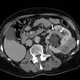

Congenital renal vein thrombosis